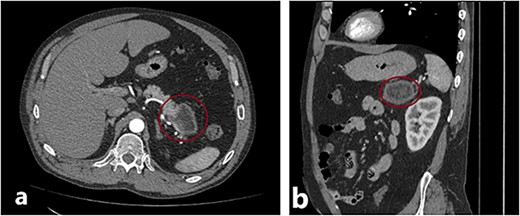

The patient, a 46-y.o. male was referred to our hospital with an already diagnosed pancreatic lesion with a diameter of ~5 cm. The patient contacted their general practitioner (GP) because of nonspecific upper-abdominal symptoms, such as vague pain in the upper abdomen, bloating, and occasional vomiting. The GP ordered an abdominal ultrasound which showed a pancreatic mass, leading to a CT scan being done. The patient’s lab results were within normal values all along. Based on the CT scan findings (Fig. 1), a decision to operate was made. A distal splenopancreatectomy being a complex procedure, a decision to try and print a 3D model of the patient’s pancreas, spleen, and surrounding vessels was reached.

(a) and (b) Axial and sagittal CT images showing a distal pancreatic tumor.